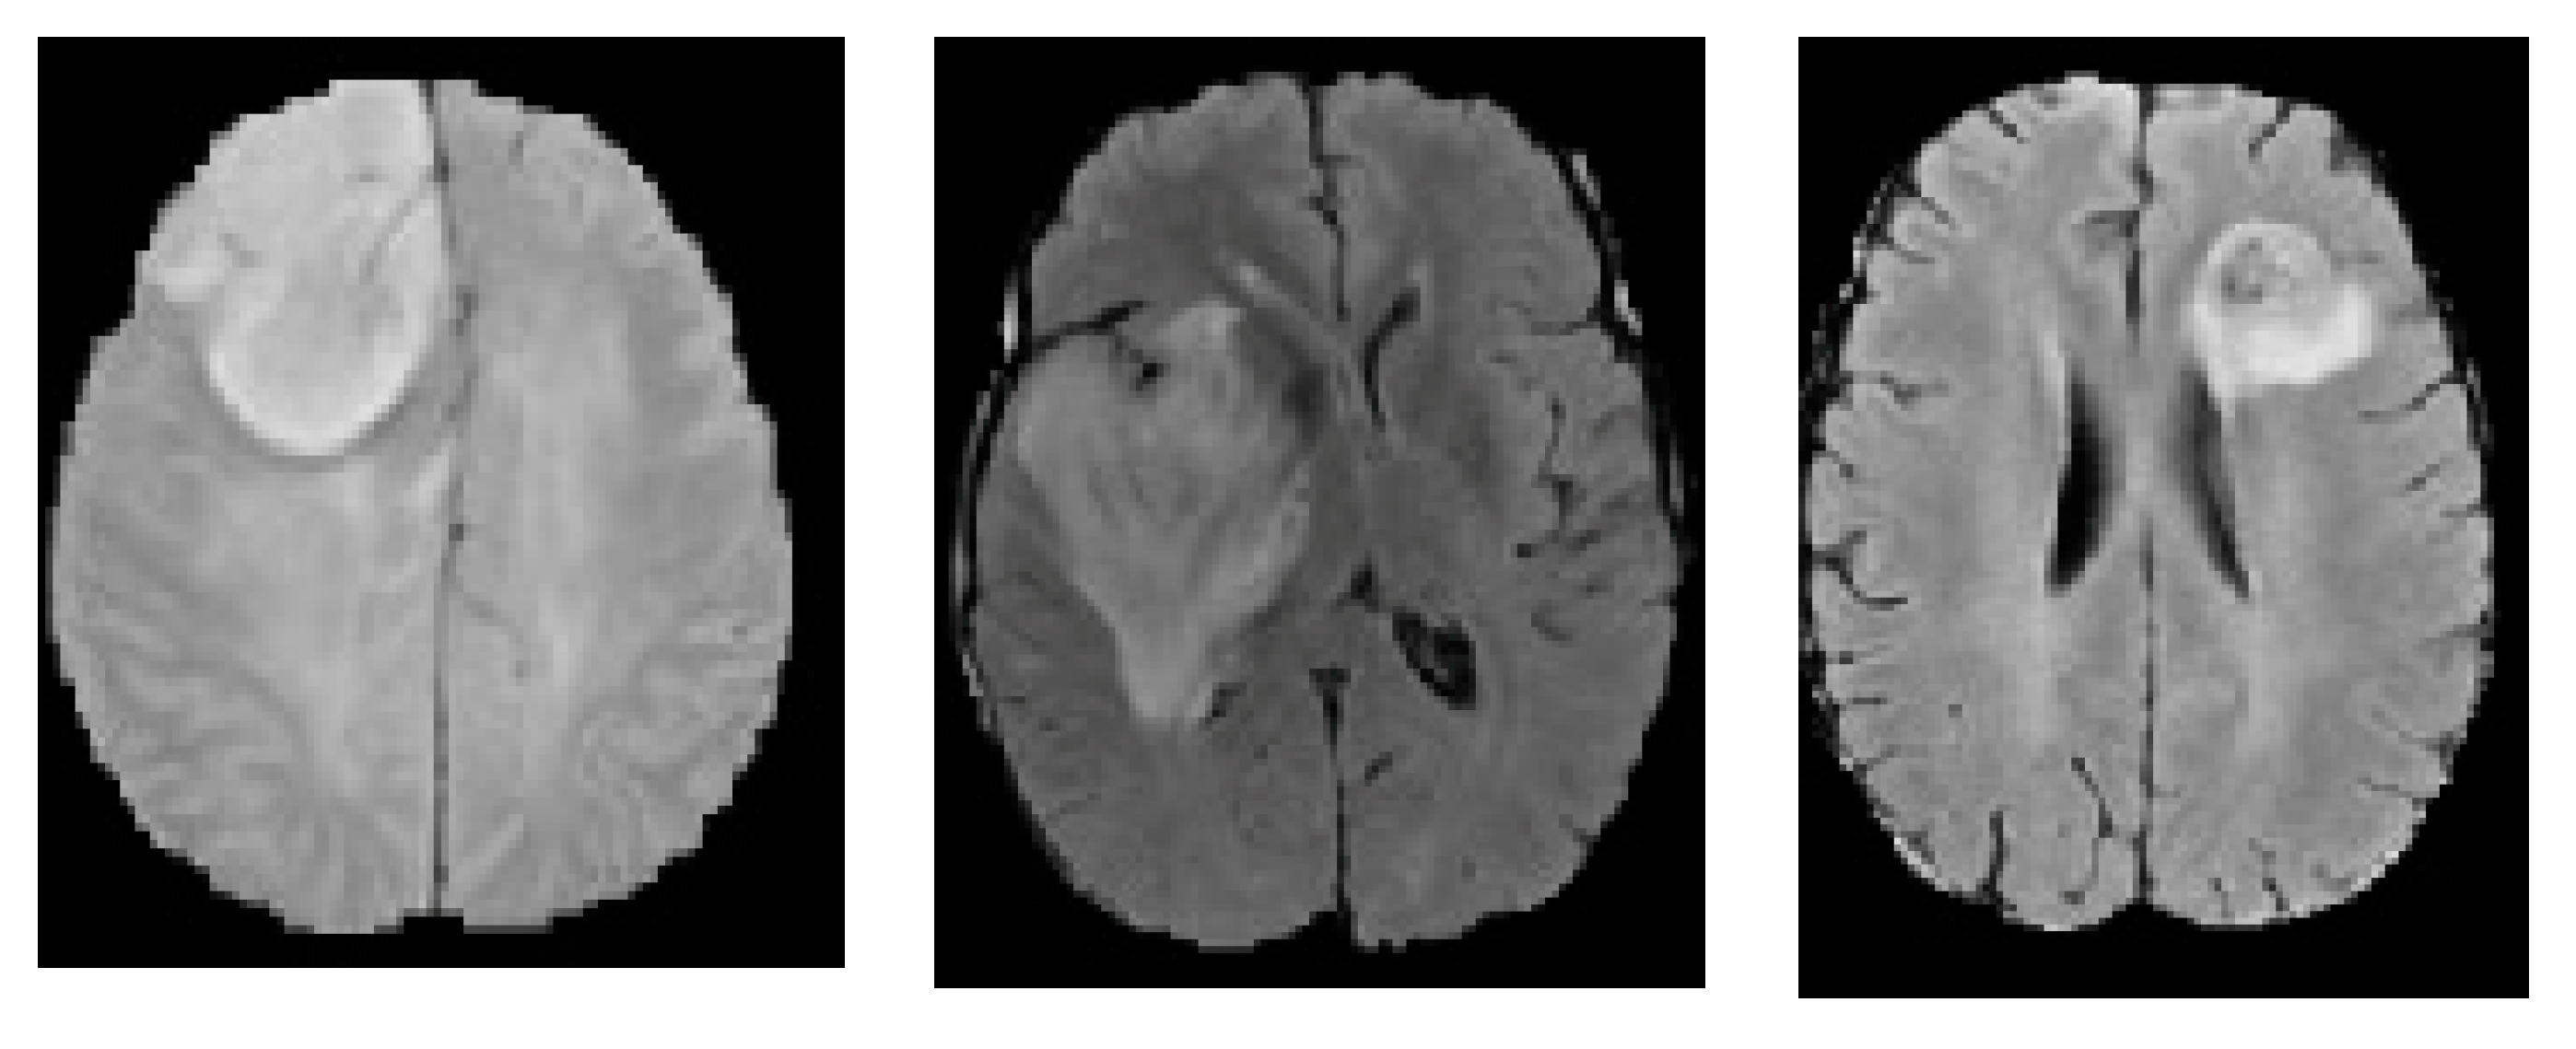

4. Experimental Results